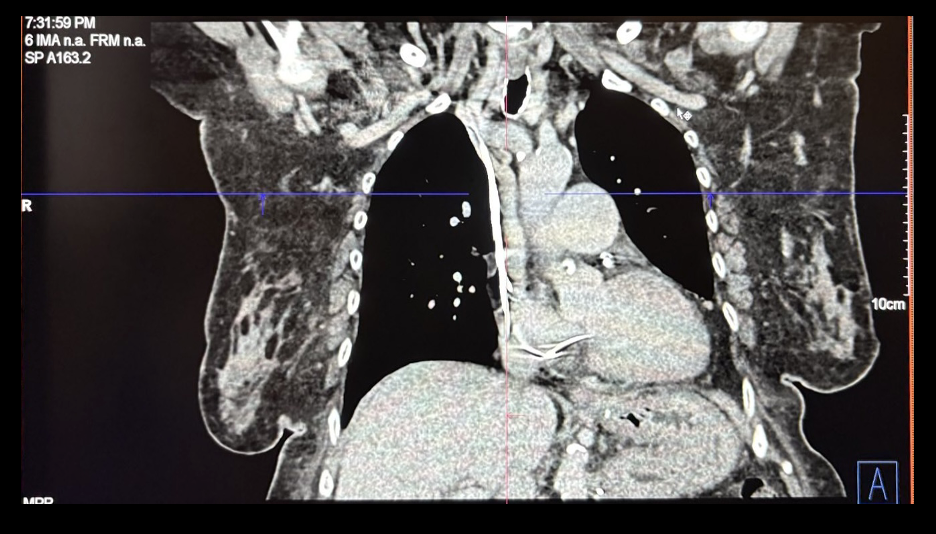

Chest CT venography revealed apparent narrowing of the left subclavian vein (red arrow) just proximal to where it crosses the first anterior ribDuplex Study of the Arteriovenous graft, left brachioaxillary graft noted patent AV fistula with computed flow rate of 2509 mL/min at the mid graft. No evidence of hemodynamically significant stenosis and thrombosis; Honeycombing pattern suggestive of subcutaneous edema